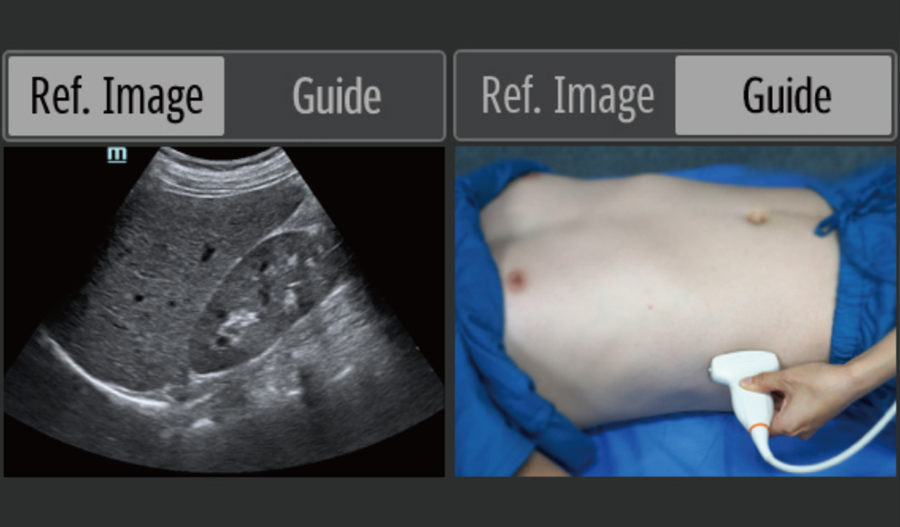

Point-of-care Ultrasound (POCUS)

The integrated ultrasound functions give a boost for on-site diagnosis, providing intelligent operation guide to make the practice all-powerful.